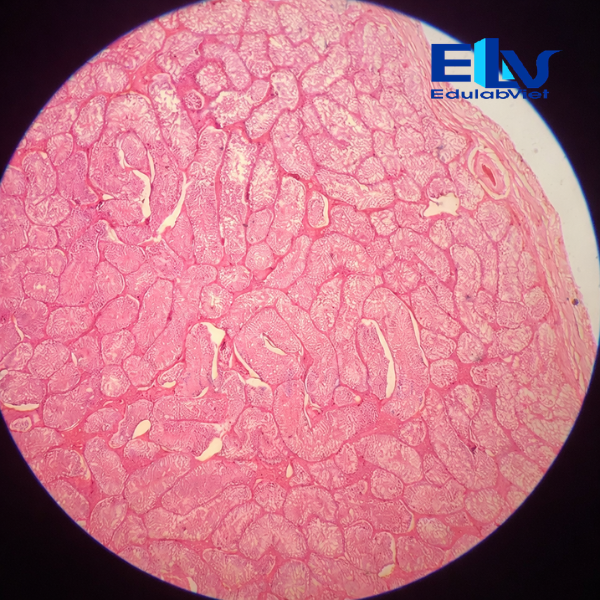

Tiêu bản tinh hoàn thỏ cắt ngang là mẫu tiêu bản hiển vi cố định thể hiện rõ cấu trúc vi thể của tinh hoàn, đặc biệt là các ống sinh tinh và các giai đoạn phát triển của tế bào sinh tinh. Sản phẩm phù hợp cho giảng dạy và thực hành môn Sinh học, Giải phẫu học, Mô học động vật.

Cấu trúc mô rõ ràng:

Quan sát rõ các ống sinh tinh, tế bào sinh tinh ở nhiều giai đoạn phát triển và mô kẽ tinh hoàn. -

Màu nhuộm đẹp – độ tương phản cao:

Tế bào được nhuộm đậm, sắc nét, giúp dễ dàng quan sát dưới kính hiển vi quang học. -